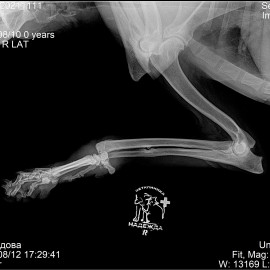

Снимки 2-3 вывих правого запястного сустава.

Снимок 4 после операции на запястном суставе.